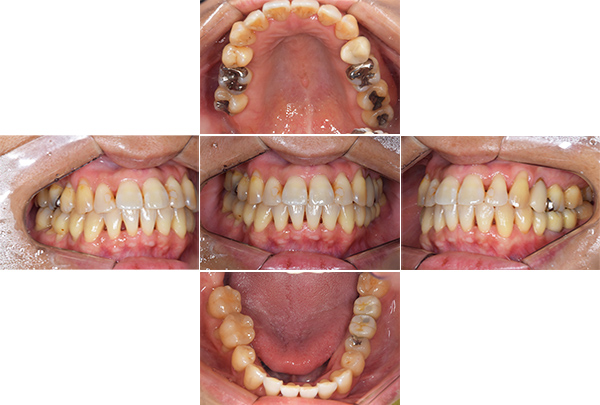

口腔内写真

【担当医師所見】

咬合平面の整頓の必要性 有

交叉咬合、オーバージェットの是正

前歯舌側の歯石

歯周病の治療の必要性

ブラッシング方法の教授